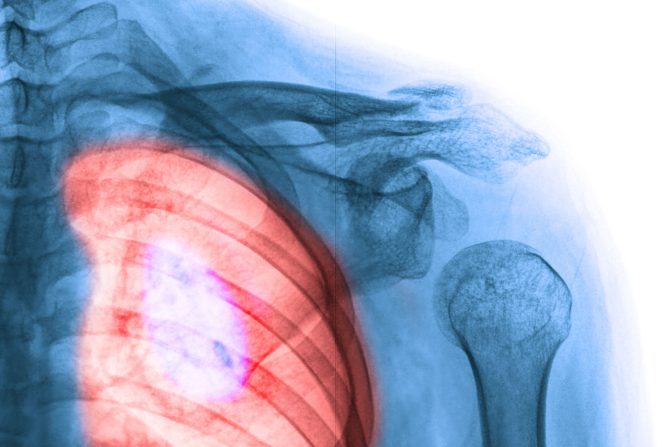

Jedna vrsta raka pluća ili adenokarcinomi ponekad reaguju na inicijalno efikasne tretmane tako što se transformišu u mnogo agresivniji sitnoćelijski karcinom pluća koji se brzo širi i ima nekoliko opcija za lečenje. Istraživači u Weill Cornell Medicine u laboratorijskim uslovima rasvetlili su ovaj problematičan proces, poznat kao histološka transformacija. Nalazi studije unapređuju saznanja kako mutirani geni mogu da pokrenu evoluciju raka i predlažu ciljeve za efikasnije tretmane.

Adenokarcinom je vrsta raka pluća koji može da se pretvori u sitnoćelijski karcinom

Sitnoćelijski ili mikrocelularni karcinom pluća je vrasta raka pluća najčešća kod pušača

Sitnoćelijski ili mikrocelularni karcinom pluća najčešće javlja kod teških pušača, ali se ovaj tip tumora razvija i kod značajnog broja pacijenata sa adenokarcinomom pluća, posebno nakon tretmana terapijama koje ciljaju na protein koji se zove receptor epidermalnog faktora rasta (EGFR), koji podstiče rast tumora. Novi tumori tipa sitnoćelijski ili mikrocelularni karcinom pluća  otporni su na anti-EGFR terapiju jer njihov rast podstiče novi pokretač karcinoma - visoki nivoi Myc proteina.